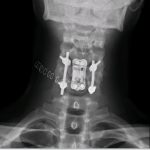

Caso clínico. Fractura C5 con compromiso posterior. Se realizó corpectomía C5 y se reconstruyó con prótesis expansible de titanio (para recuperar lordosis) + placa cervical anterior. Se asoció fijación posterior en un segundo tiempo, tras darle la vuelta al paciente.